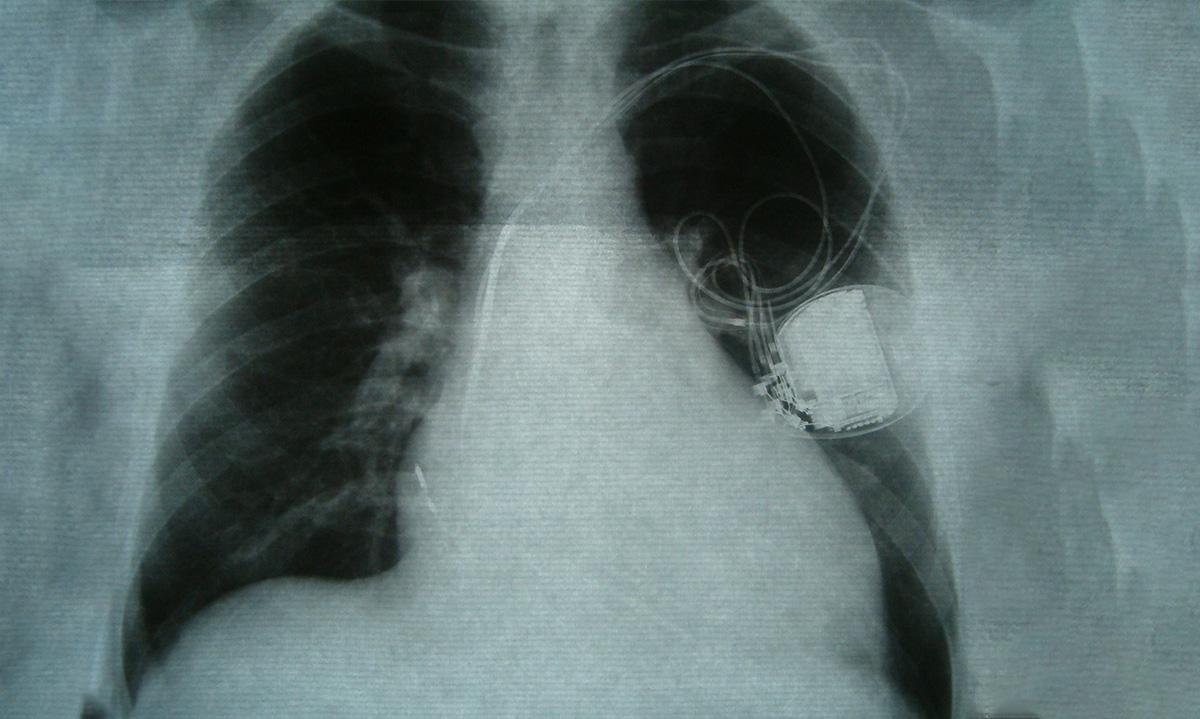

The new funds will enable CorWave to complete the development of its wave membrane pump LVAD (Left Ventricular Assist Device). The company plans to use its latest funding to expand its manufacturing infrastructure as well as complete the regulatory testing required to conduct human implants and start clinical trials for advanced heart failure.

CorWave has achieved two critical technical milestones required to proceed to the clinical phase: a successful 60-day in vivo implant, with excellent hemocompatibility results, and the completion of 6-month real-time durability tests of the pump.

CorWave is a French company developing innovative cardiac assist devices. Its technology stands out from other LVADs (left ventricular assist devices) currently on the market due to its physiologic design, which is enabled by its disruptive wave membrane. The membrane is able to generate a natural pulse, replicating the blood flow and pressure characteristics of the patient’s native heart. CorWave’s novel membrane pump technology is being developed to reduce complications associated with current devices and improve the care of patients with heart failure. CorWave was incorporated in 2012 by the startup studio MD Start and is funded by well-known investors, including Bpifrance, Novo Holdings, Seventure, Sofinnova Partners, and Ysios. The company had secured over 45 million euros of equity and non-dilutive funding prior to its Series C round and employs more than 50 people. www.corwave.com

Heart failure corresponds to the loss of contractility of the heart. The heart muscle is too weak and cannot eject enough blood to the needs of the body. It does not pump sufficient blood flow through the body to meet the physiological needs of the body and in particular other vital organs such as the kidneys and the liver. This pathology is progressive and worsens over time, as the heart weakens further while trying to compensate for its loss of activity.